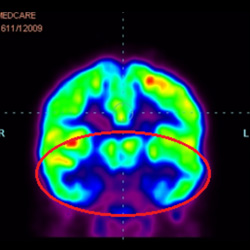

細(xì)胞治療前 PET CT 掃描顯示神經(jīng)組織中的藍(lán)/黑色區(qū)域,表明腦癱引起的大腦損傷。

腦癱細(xì)胞療法, 腦癱治療

細(xì)胞治療后,藍(lán)色和黑色區(qū)域減少,并且看到更活躍的區(qū)域。這表明損傷減少并改善了大腦功能。